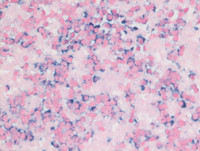

Figure 1: HE images

Low power images demonstrate sheets of neoplastic lymphoid/plasmacytic cells with associated pink amorphous hyaline deposits identified to be amyloid. On higher power, the neoplastic cells are unusually small plasma cells with "lymphocyte-like" cytomorphology.